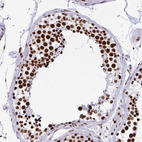

Immunohistochemical staining of human gastrointestinal, kidney, squamous epithelia and testis using Anti-EWSR1 antibody HPA062953 (A) shows similar protein distribution across tissues to independent antibody HPA051771 (B).